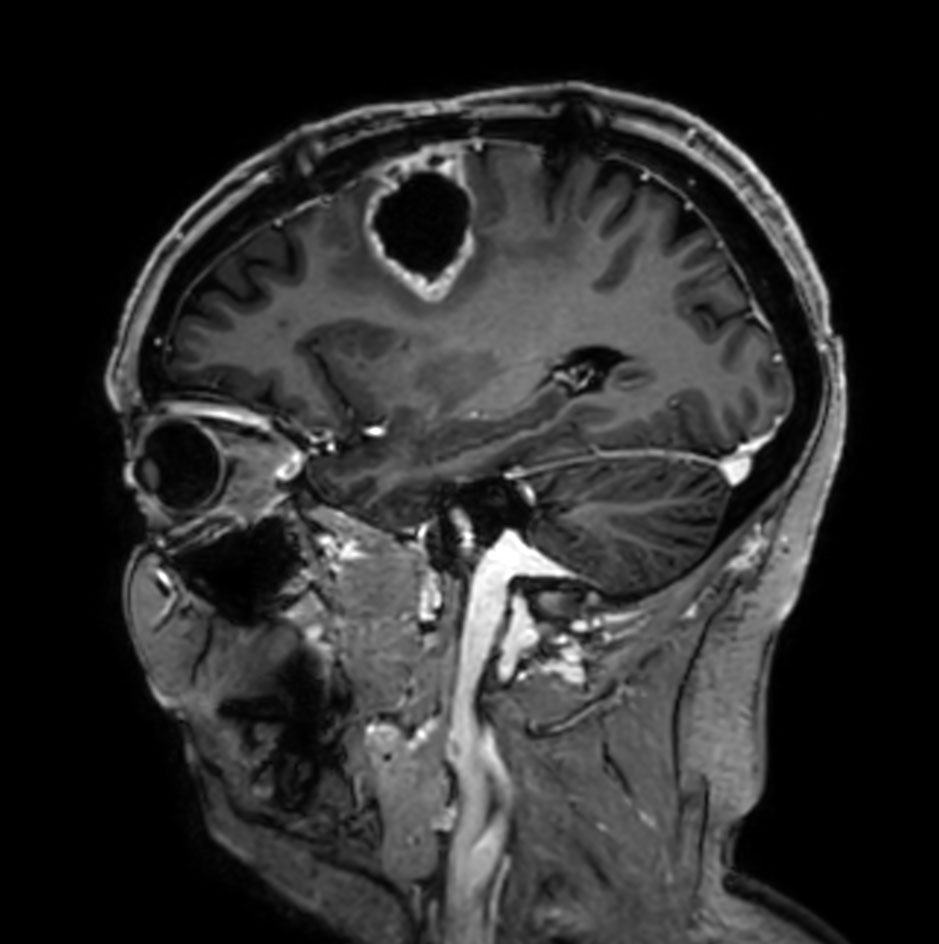

Sagittal 3D T1w TFE

Sagittal 3D T1w TFE (with gado)